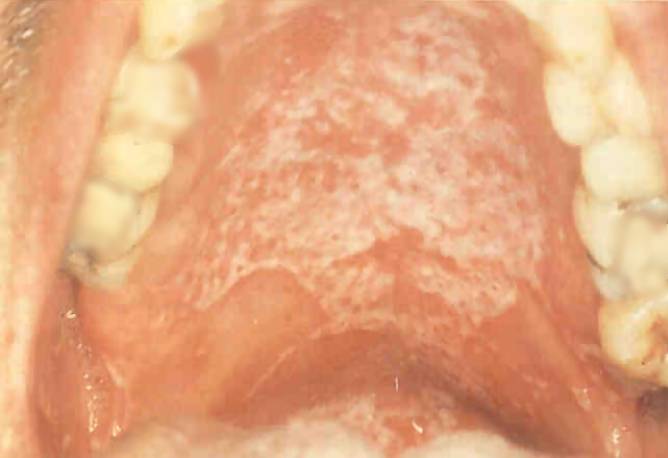

Szájpenész

A beteg szájpadlása (fent) és nyelve (lent) mutatják a szájpenészt, egy opportunista gombás fertőzést.